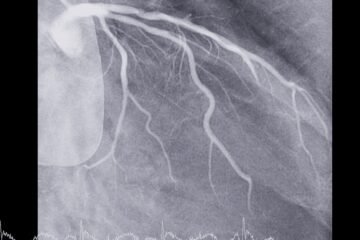

Attēldiagnostika

- Datortomogrāfiju izmanto vēdera dobuma un iegurņa izvērtēšanai. Virtuālā kolonoskopija, kas balstīta uz datortomogrāfiju, var kalpot kā alternatīva, ja standarta kolonoskopiju nav iespējams veikt.

- Magnētiskā rezonanse var tikt izmantota aknu izvērtēšanai, ja pastāv aizdomas par slimības izplatību.

- Rentgenoloģiska izmeklēšana krūškurvim tiek veikta gadījumos, kad nepieciešams novērtēt iespējamu izplatību uz citiem orgāniem.

- Pozitronu emisijas tomogrāfiju pielieto retāk, biežāk sarežģītās situācijās, lai precizētu izplatību.